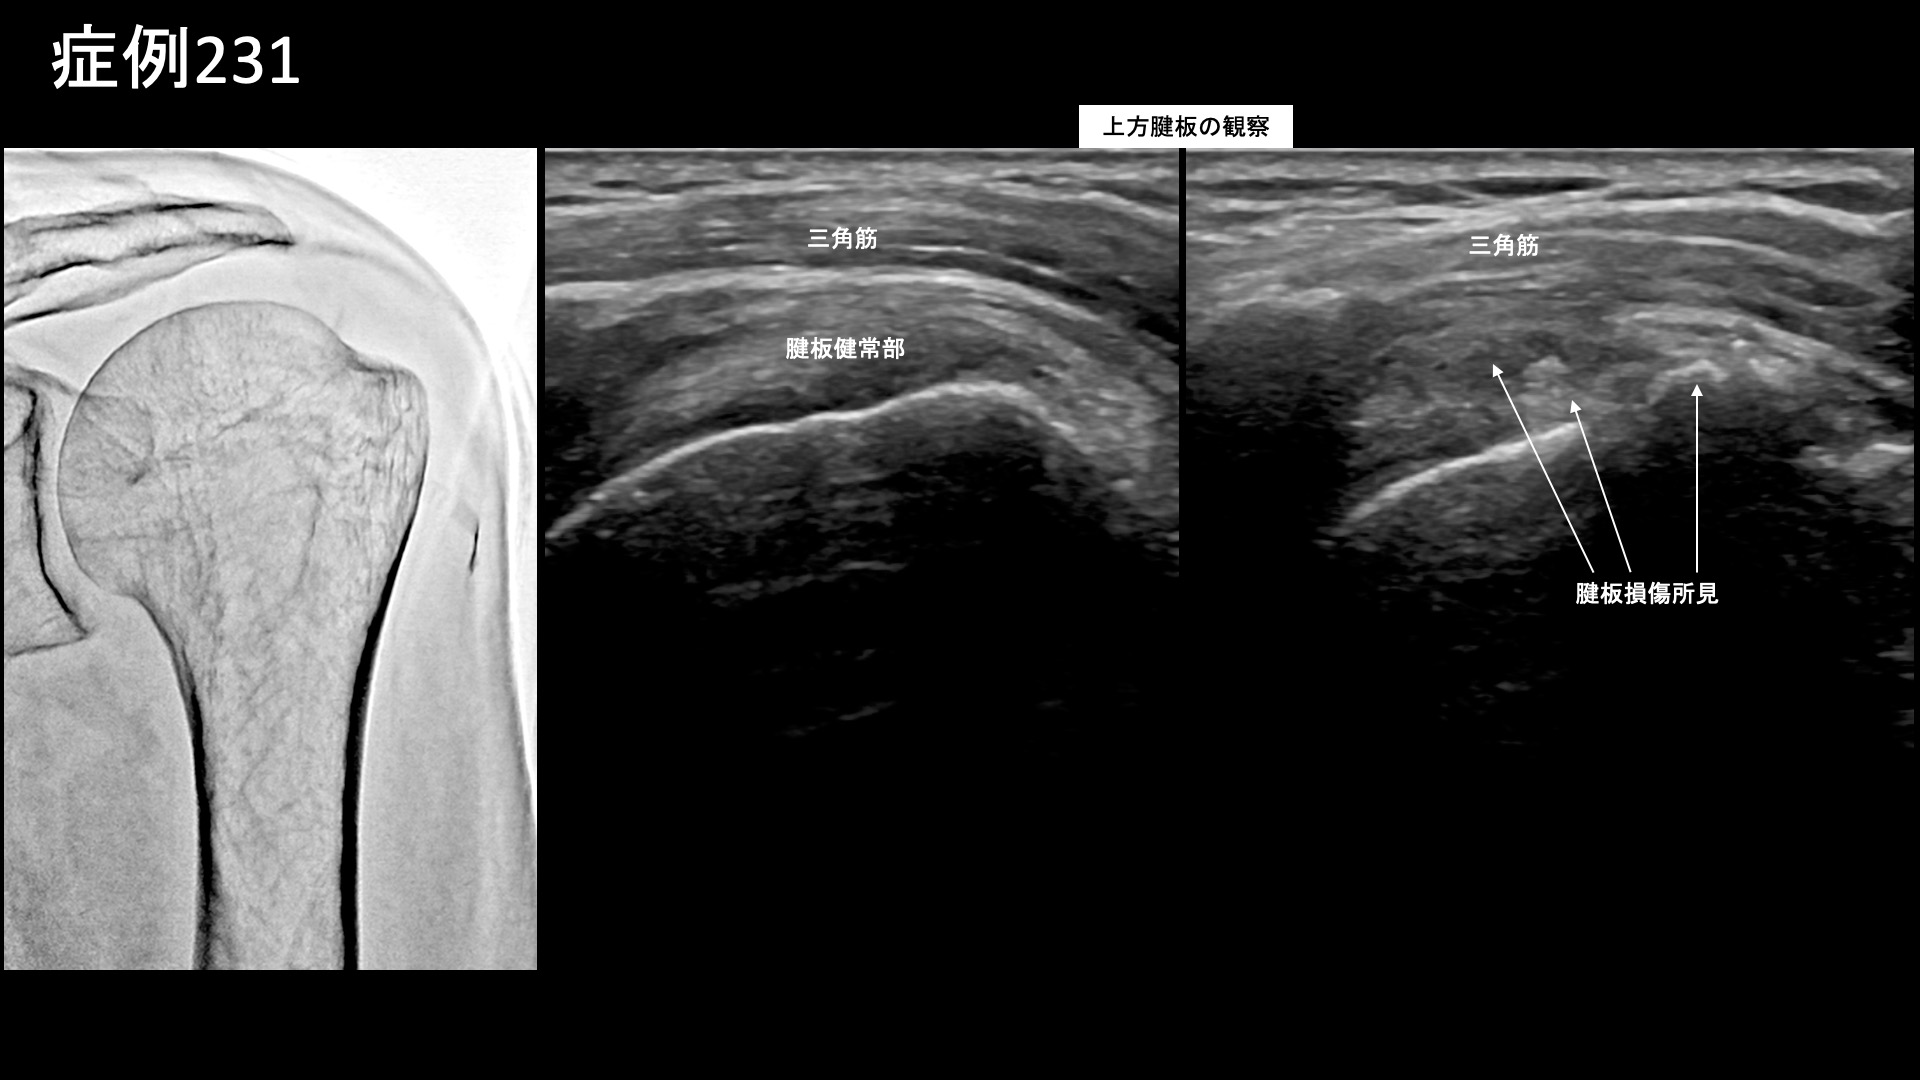

肩:肩こり・四十肩・五十肩 【50代:男性】肩腱板断裂手術後の遺残痛、及び再断裂による痛みに対するモヤモヤ血管治療(腱板断裂、手術後遺症、再断裂、肩関節周囲炎) 2025.08.26 鴨井院長による動画解説 受診までの経過 荷物運搬などの重労働により1年半前から左肩が痛むようになり、MRI検査で腱板断裂と診断されました。腕が全く上がらなくなってしまい、10ヶ月前に手術を受けました。入院は1ヶ月に及びましたが、腕が挙がるようになりました。しかし、痛みがとれず、じっとしていればよいものの、動かすと痛みが生じていました。MRI検査では、手術で縫合した部分の一部に再断裂を指摘されていました。リハビリを続けていましたが、リハビリで痛みを良くすることはできないと言われ、当院を受診されました。 診察時の所見 肩関節の可動域をチェックすると、外転、屈曲で軽度の制限がありましたが、日常生活には支障をきたさないくらいに保たれていました。レントゲンでは特に異常はありませんでした。エコー検査をすると、肩関節の前方において、腱板疎部や上腕二頭筋長頭腱周囲にモヤモヤ血管を反映した異常血流信号を認めたほか、上方腱板に断裂所見を認めました。腱板断裂後、手術により可動域は改善したものの、一定の痛みが残存し、さらに再断裂に伴う炎症も相加されている状態でした。治療適応と判断し、モヤモヤ血管(病的新生血管)に対する運動器カテーテル治療(微細動脈塞栓術)を受けていただきました。 治療の所見 血管造影を行うと、胸肩峰動脈でモヤモヤ血管が濃染像として描出されました。治療後は画像上速やかに消失しました。その他複数個所の治療を行い終了しました。 治療後の経過 治療後1週間で、左上腕の痛みが消失しました。肩関節前方の痛みはまだ残っていましたが、それも1ヶ月経過するうちに無くなりました。治療後2ヶ月、元々の痛みは取れた感じがする一方で、痛くなかった部位が少し痛み、特に腕を前方に伸ばしたときに痛みがありました。術前に比べればかなり楽になっており、日常生活での支障はないとのことでした。治療後3ヶ月、痛みはほぼ消失しました。前述の痛みがまだ多少残っているものの、自然軽快が見込まれたため、終診としました。腱板断裂による痛みについては、8-9割の痛みが取れて日常生活に支障をきたさなくなった後も、完全に消失するには半年~1年かかることもあります。その内に気にならなくなり、いつの間にか治っているという感覚になる方もおられます。 本症例では、肩関節への過負荷が原因でした。手術後の再断裂リスクは新規の断裂よりも高いのですが、お仕事柄、今後も過負荷による再断裂が懸念されます。無理を重ねないよう、慎重にお過ごしいただきたいと思います。 腱板疾患の詳しい病状説明はこちら 【60代:男性】ゴルフのフルスイングで生じる腰痛。仙腸関節障害に対するカテーテル治療(仙腸関節障害、筋・筋膜性疼痛症候群) 前の記事 【50代:男性】新型コロナウイルスワクチン接種後、鬼の手に⁉ 誰にも理解してもらえず3年間苦しんだ両肩~両手指の痛み(新型コロナウイルスワクチン接種後遺症、副反応、SIRVA、肩関節周囲炎、手指変形性関節症) 次の記事